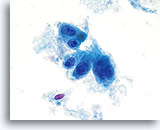

Celkernmembranen zijn verdikt en onregelmatigheden in celkernmembranen zijn golvend, in tegenstelling tot de “rattenbeet”-membranen die ook wel in squameuze laesies gezien wordt.

40x